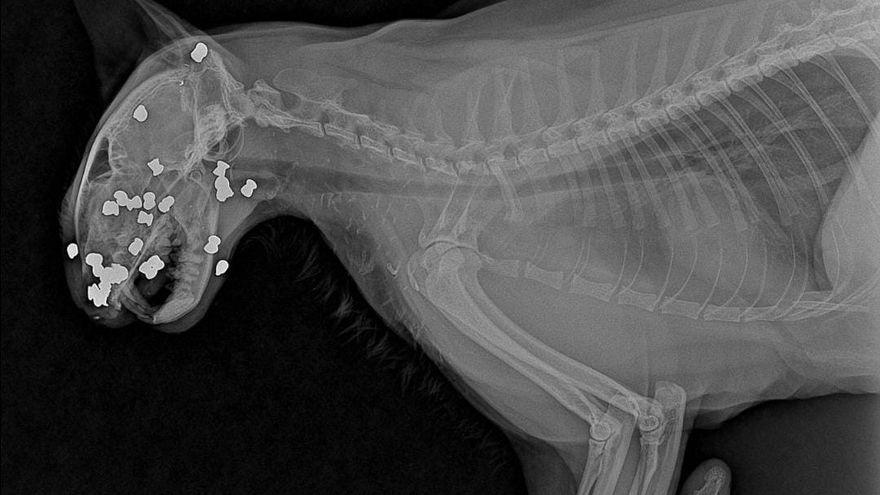

El Colegio Nacional de Abogados (Comisión de Protección y Derecho Animal) en conjunto con una empresa privada anunció una recompensa de 100$ a quien presente evidencias de quién disparó más de 30 veces con una pistola de balines a un gato, causándole la muerte.

El Club de Gatos de Panamá, dio a conocer que el indefenso animal fue encontrado en la Avenida 8B norte en de Betania.